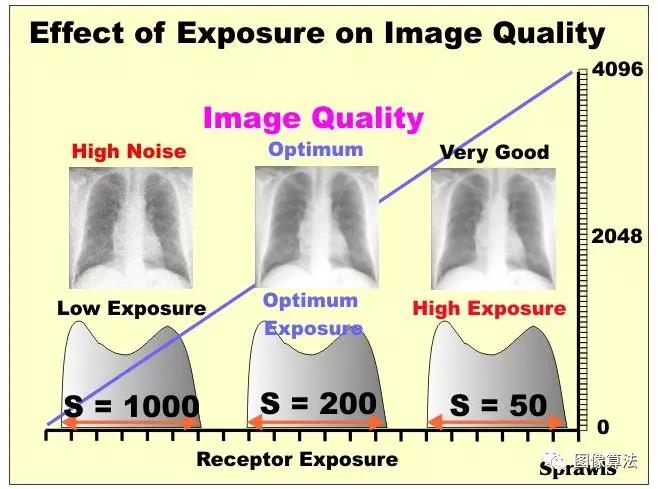

过量的量子噪声是数字放射成像中的潜在问题,因为就对比度而言,可以产生具有低曝光的图像,其仍然看起来很好。下面通过曝光动态范围下端附近左侧的图像说明该条件。对比度仍然很好,但噪音是两个高。

原则上,数字射线照相系统在曝光后设置其灵敏度(速度),以便校正实际曝光。

在数字放射成像中,重要的是对每个程序使用适当的曝光和技术因素。最佳(正确)曝光是产生具有可接受的噪声水平的图像而没有不必要或过度暴露于患者的图像。

数字射线照相系统与图像一起显示,以及用于形成图像的曝光量的指示。各种制造商使用不同的因素来显示曝光信息。下面说明了一个制造商使用的“S”因子。与图像一起显示的“S”值表示系统对该特定图像使用的效果灵敏度(速度)。

高S因子(如1000)表明图像是以低曝光形成的,并且预计会产生过多的噪声。低S因子(如50)表示使用了不必要的高曝光。由于噪音低,图像质量良好,但患者遭受不必要的曝光。

在数字射线照相受体的宽动态范围内产生不同曝光的图像。